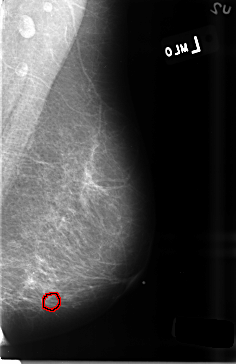

B_3470_1.RIGHT_MLO

FILE: B_3470_1.LEFT_MLO.OVERLAY

TOTAL_ABNORMALITIES 1

ABNORMALITY 1

LESION_TYPE CALCIFICATION TYPE PUNCTATE-PLEOMORPHIC DISTRIBUTION CLUSTERED

ASSESSMENT 4

SUBTLETY 2

PATHOLOGY BENIGN

TOTAL_OUTLINES 1

BOUNDARY